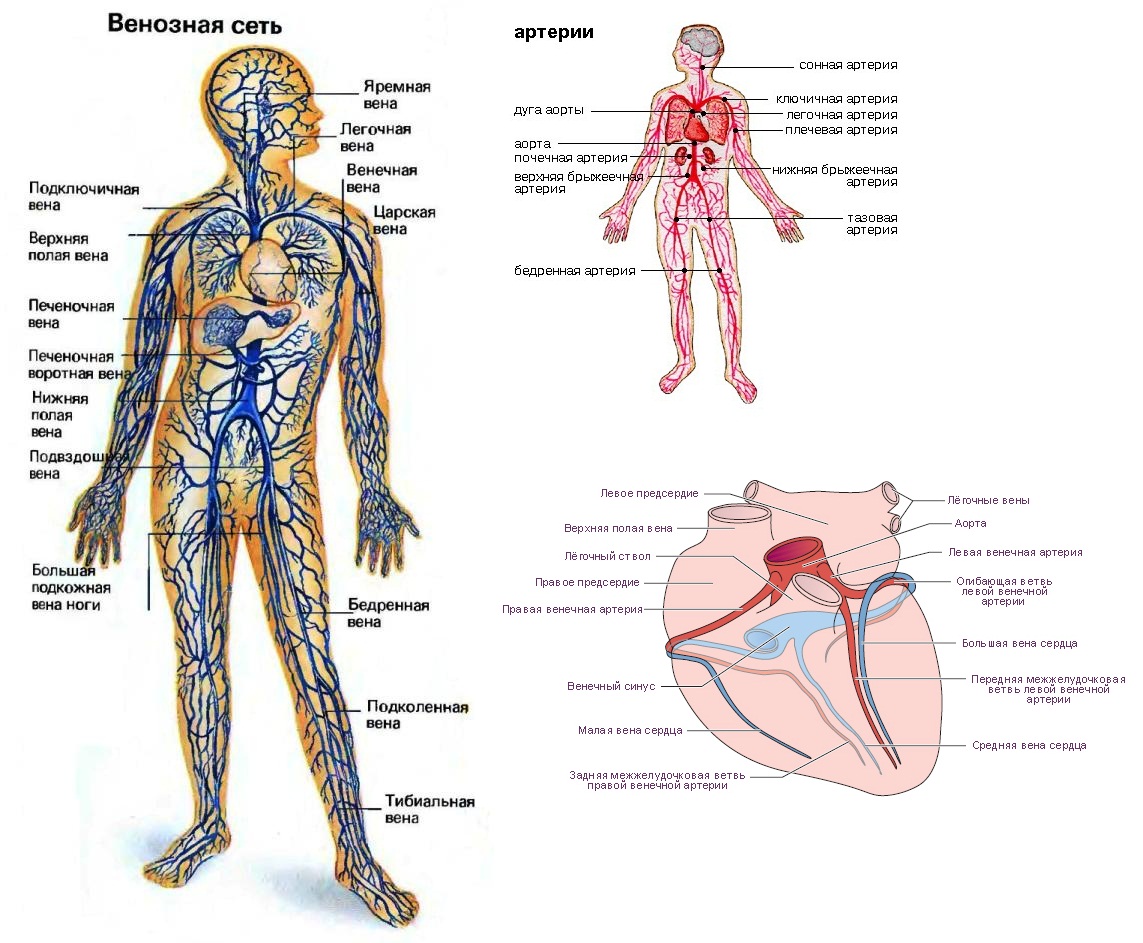

Кровеносная система человека: структура и функции